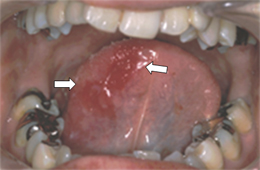

●舌にできた紅板症

紅板症の50%前後が悪性化するといわれています。

外科的に切除するのが望ましいとされています。

悪性化する可能性が高いため、治療後にも経過観察を行う必要があります。